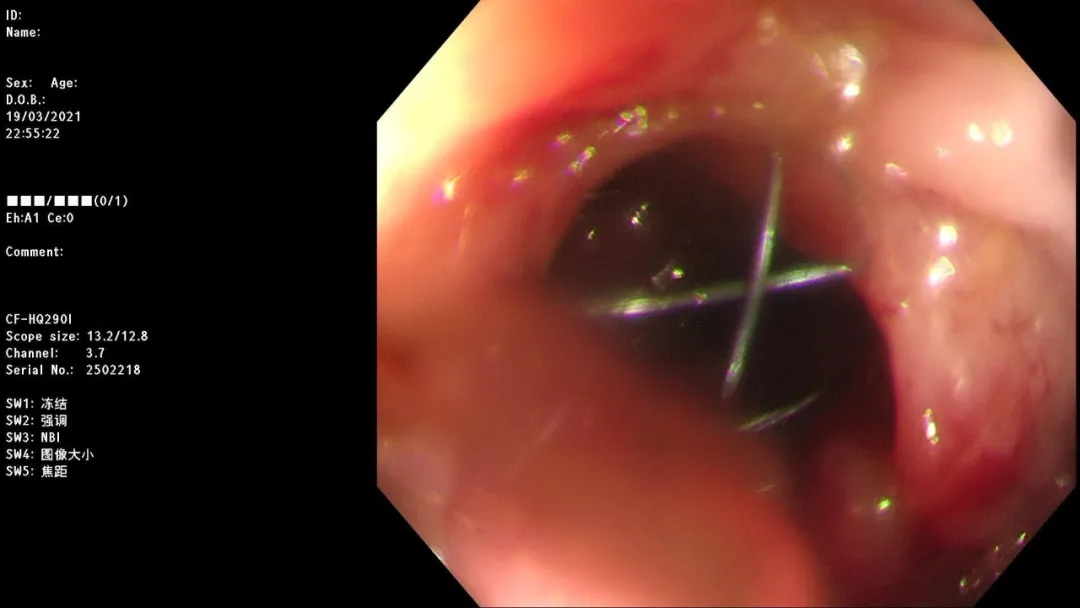

急诊肠镜示:距肛门20cm新生物,占据肠腔全周,放入肠道支架通过狭窄段,粪水流出,检查诊断:乙状结肠癌并梗阻急诊肠道支架置入术。